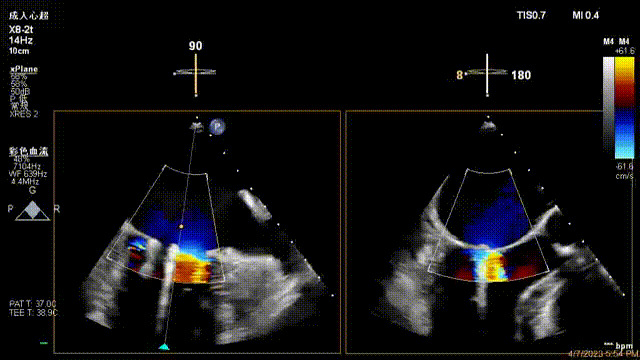

接受治療的是一例器質(zhì)性重度二尖瓣反流(DMR)患者,主訴“反復(fù)活動后胸悶,氣促3年余”。術(shù)前超聲顯示,雙房增大,二尖瓣脫垂伴重度反流,輕度三尖瓣反流,輕度肺高壓,升主動脈增寬。手術(shù)經(jīng)股靜脈-房間隔入路,采用全身麻醉插管,在TEE和DSA引導(dǎo)下完成房間隔穿刺。置入JensClip瓣膜夾系統(tǒng)后,在左房調(diào)整瓣膜夾的位置和軸向,后進(jìn)入左室,在TEE引導(dǎo)下捕捉二尖瓣前后瓣葉,并關(guān)閉瓣膜夾。經(jīng)TEE反復(fù)確認(rèn)手術(shù)效果后最終鎖定并釋放瓣膜夾。術(shù)后即刻超聲顯示瓣膜夾位置穩(wěn)定,功能良好,術(shù)前二尖瓣反流4+,術(shù)后0反流,肺靜脈逆流和左房壓都顯著好轉(zhuǎn),手術(shù)圓滿成功(以上數(shù)據(jù)都來源于醫(yī)院的臨床記錄)。術(shù)后患者狀態(tài)良好,目前已安排出院。

術(shù)前超聲提示二尖瓣重度反流